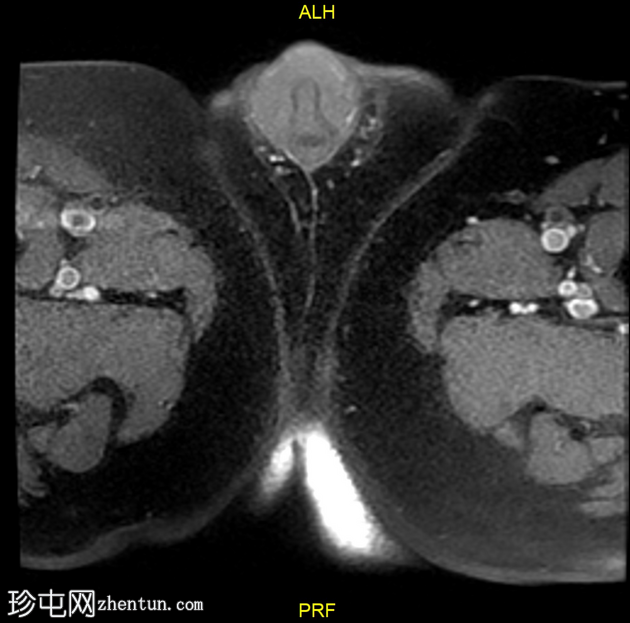

2.jpg

轴位

T1加权像

龟头可见不规则形状的软组织肿块,增强后明显强化,并伴有扩散受限。该肿块侵犯尿道海绵体,导致远端尿道狭窄和上游尿道扩张。

左侧腹股沟可见多个肿大的病理性淋巴结,右侧可见较小的非特异性淋巴结。